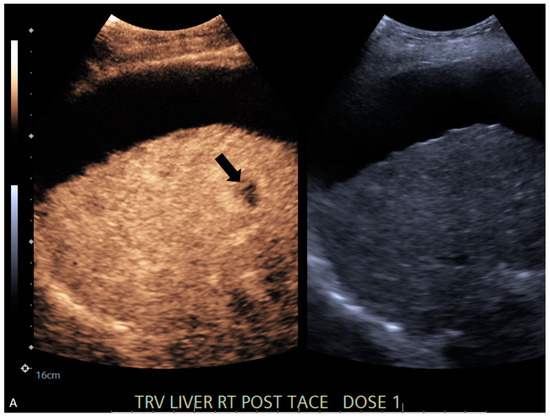

| 4 | CT | Target | LR-treated | CEUS called residual tumor (Figure 1), follow-up CT confirmed treated tumor |